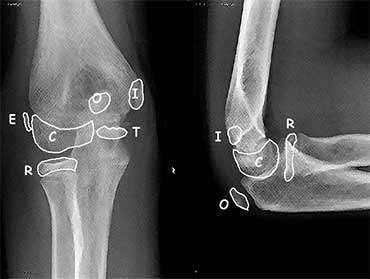

Knowledge of ossification centers of the elbow can be helpful (see Elbow X-ray)

Elbow Ossification by Age (CRITOE)

| Ossification Center | Age of Appearance (add 1yr for boys) |

| Capitellum | 1yr |

| Radial head | 3yr |

| Internal epicondyle | 5yr |

| Trochlea | 7yr |

| Olecranon | 9yr |

| External epicondyle | 11yr |